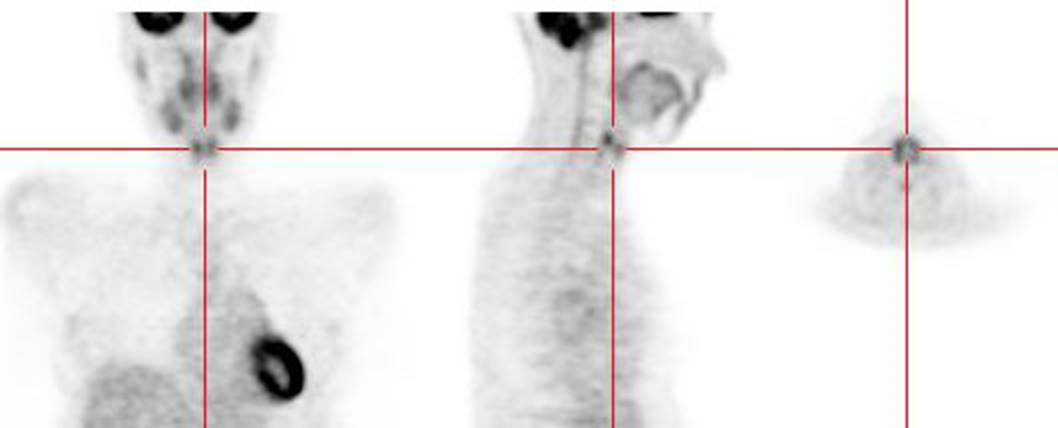

Figure 11 - Brown Fat: Prominent, symmetric

supraclavicular tracer uptake was seen in this patient without a corresponding

CT finding. Uptake in this area has been felt to be related to the presence of

"brown" fat.